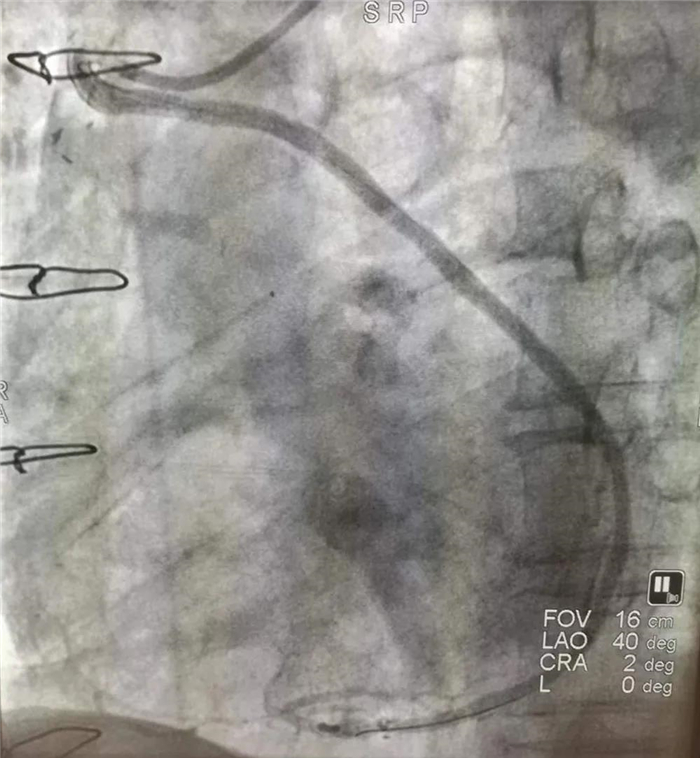

8月31日一大早,家住吴台镇的50岁的赵某突发胸痛,持续加剧,直至痛得大汗淋漓。上午8时36分,赵某到达县人民医院,在急诊科行心电图,显示急性下壁心肌梗死。在给予患者口服药的同时,一键启动胸痛中心绿色通道,患者直接到达导管室,于8时58分开始行急诊冠脉造影。

“冠脉造影就是通过造影剂使血管显影,查找血管堵塞的精准位置,这样才能进行下一步的治疗。”郸城县人民医院副院长、心血管介入专家郭环宇说,“这例手术难就难在血管造影,因为患者于六年前曾做过心脏搭桥。”所谓搭桥,就是心脏血管发生严重堵塞后,截取下肢的一段血管,连接到堵塞血管的两端,相当于在堵塞处搭建一个“桥梁”,恢复血液畅通。

但是,6年前做过的搭桥,具体在什么位置,现在已很难查找,在胸腔内状如蛛网的血管中,要准确找到搭桥位置,难乎其难,常常需要数小时才能准确找到桥血管。郭环宇具有丰富的经验,在助手王健、朱乾坤配合下,仅半个多小时就已查明。9时32分造影结束,决定对右冠桥血管病变行支架植入术(PCI)。

在“桥”上放支架,比普通冠心病患者的支架植入要难得多。但县人民医院胸痛中心自建设以来,每年实施支架植入术千余例,技术已十分娴熟。40多分钟后,手术顺利结束,桥血管恢复畅通,患者胸痛症状缓解。10时15分,患者入住CCU病房观察治疗。